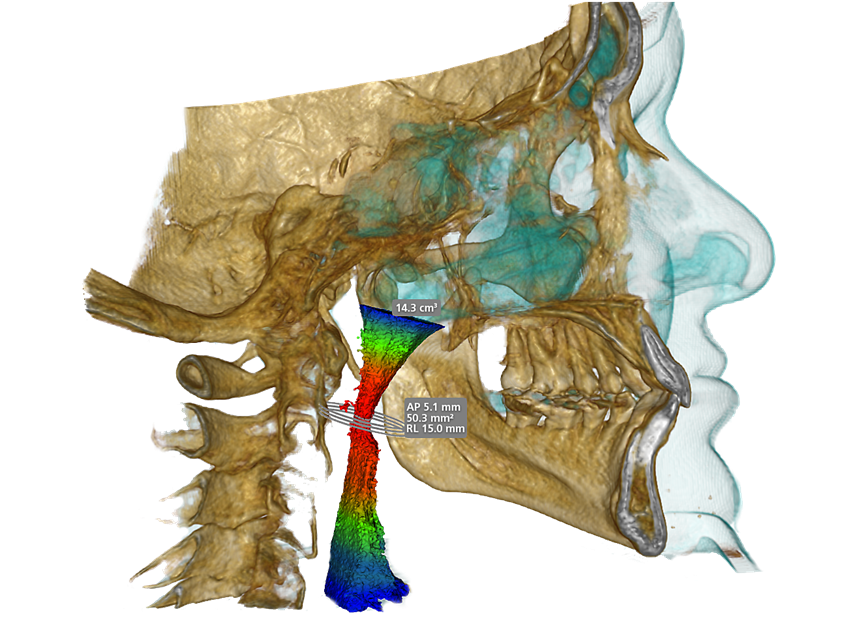

Cone Beam Computed Tomography (CBCT)

Special 3D imaging technique that provides detailed images of teeth, jaws, nerves, and surrounding structures. CBCT is quick, accurate, and offers 3 Dimensional knowledge compared to normal X-rays, ensuring better care for complex dental issues.

Temporomandibular Jaw Analysis

Airway Analysis

TMJ Assessment